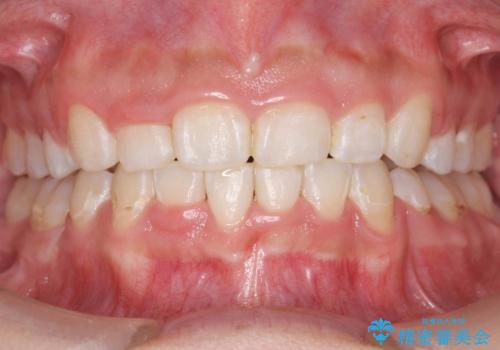

前歯のがたがた 前歯が内側に傾いている

- 治療期間

- 2年3ヶ月

- 前歯のがたがたを主訴に来院。

上の歯並びが前にずれて、さらに前歯が内側に倒れて過蓋咬合を呈していました。

奥歯のかみ合わせもずれていたため、上の奥歯を後ろに下げる処置をミニスクリューを用いて行いました。